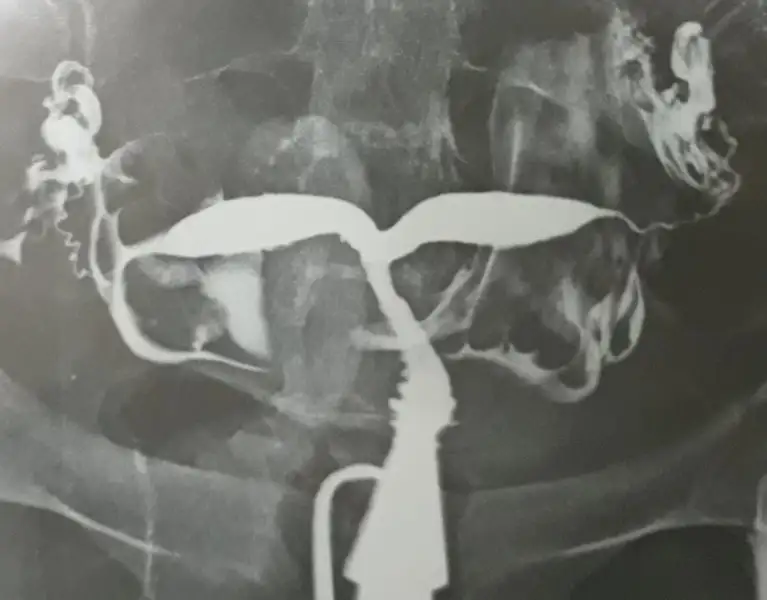

Rahim filmim bu sonucuda uterin kaviteler ayrık izlenmekte olup bikornis unikollis veya parsiyel septat uterusa bağlı değişiklikler temsil edebilir ... sonuc// endometriyal kaviteler arasındaki myometriumun durumunun pelvik mr bulguları ile birlikte değerlendirilmesi ve gereklilik halinde laparoskopik tetkiki önerilir yazıyor

Eklentiler

• 20171122_133148.webp

20171122_133148.webp

12 KB · Görüntüleme: 198